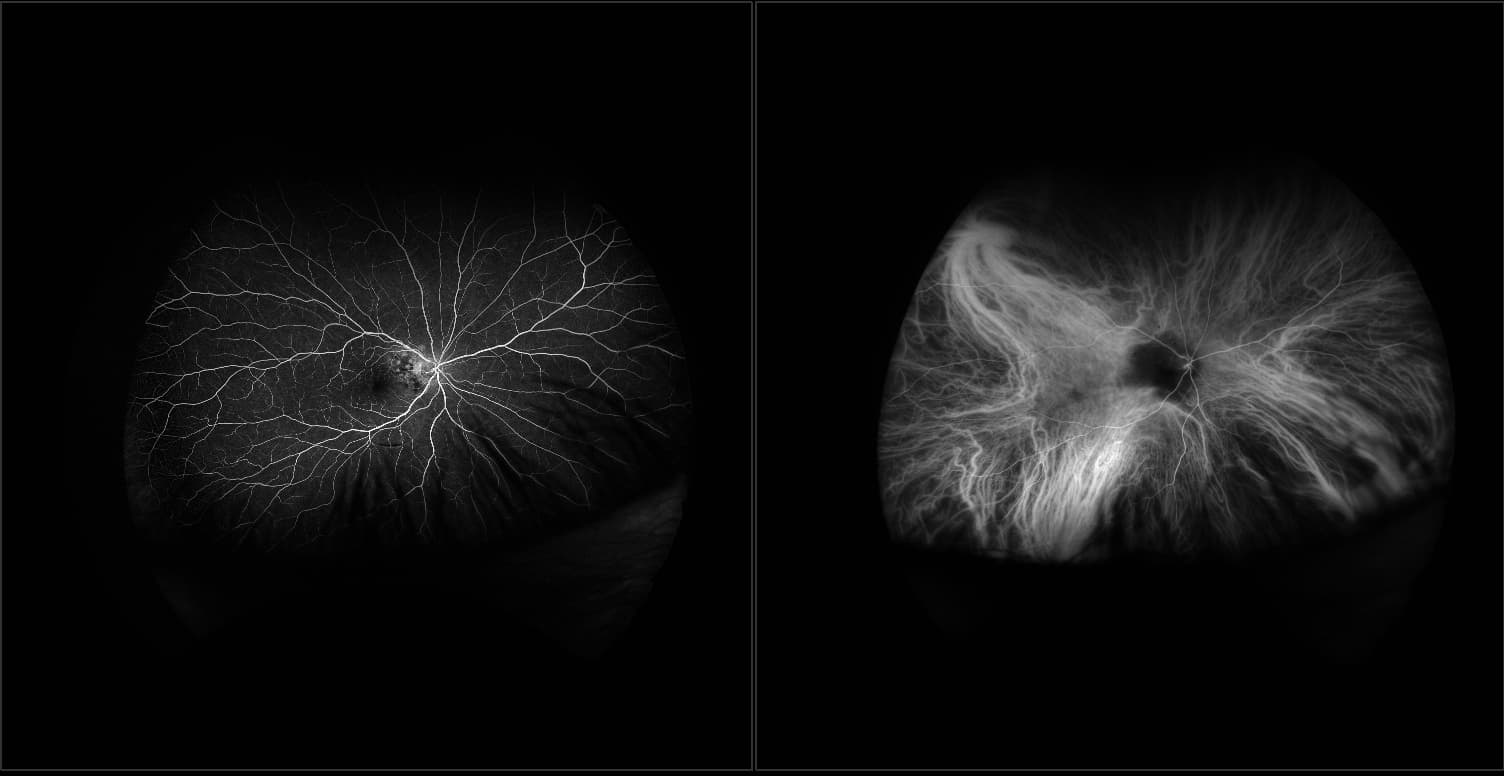

California - Choroidal Nevus, RG, AF

A choroidal nevus is simply an accumulation of melanocytes in the choroid. They are a space occupying mass or a benign melanoma. Choroidal nevi are slate gray in color, have indistinct margins, and may be slightly elevated (1-2 diopters). Since they are in the choroid, they are usually only seen in the red separation and not the green. The green separation may show the RPE degeneration associated with nevi which is seen as pigment mottling and drusen.